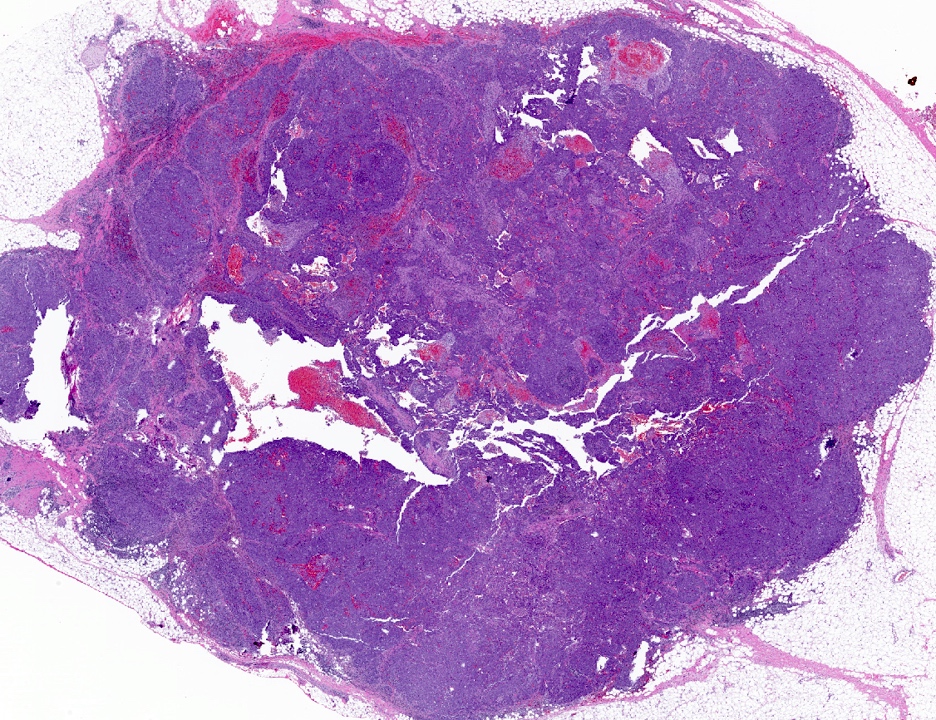

Microscopic (histologic) description

- Luminal

- Invasive ductal carcinoma, no special type (IDC, NST)

- HER2 enriched

- Predominantly IDC, NST of high histological grade

- Frequently associated with high grade comedo ductal carcinoma in situ